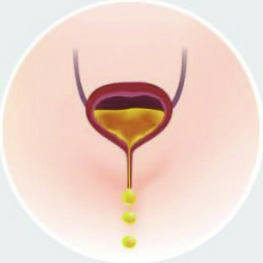

- GIẢM TIỂU KHÔNG TỰ CHỦ

Tiểu không tự chủ (UI) - tình trạng mất kiểm soát bàng quang - là một vấn đề phổ biến và thường gây khó chịu. Đây là một triệu chứng do nhiều nguyên nhân gây ra, bao gồm sinh nở, mang thai, lão hóa, cắt bỏ tử cung, mãn kinh và các rối loạn thần kinh.

+ NAM GIỚI

15% Nam giới bị ảnh hưởng bởi UI ở độ tuổi trên 60.

+ NỮ GIỚI

60% Phụ nữ bị ảnh hưởng bởi UI ở độ tuổi từ 45 đến 55.

TRƯỚC

Các cơ sàn chậu không đủ khả năng hỗ trợ các cơ quan vùng chậu và ảnh hưởng đến khả năng kiểm soát bàng quang.

ĐIỀU TRỊ

Bàn tập cơ sàn chậu kích thích hiệu quả các cơ sàn chậu với hàng ngàn con co thắt cơ mỗi lần điều trị.

SAU ĐIỀU TRỊ

Kích thích làm khỏe cơ sàn chậu, giúp lấy lại khả năng kiểm soát các cơ sàn chậu và bàng quang.